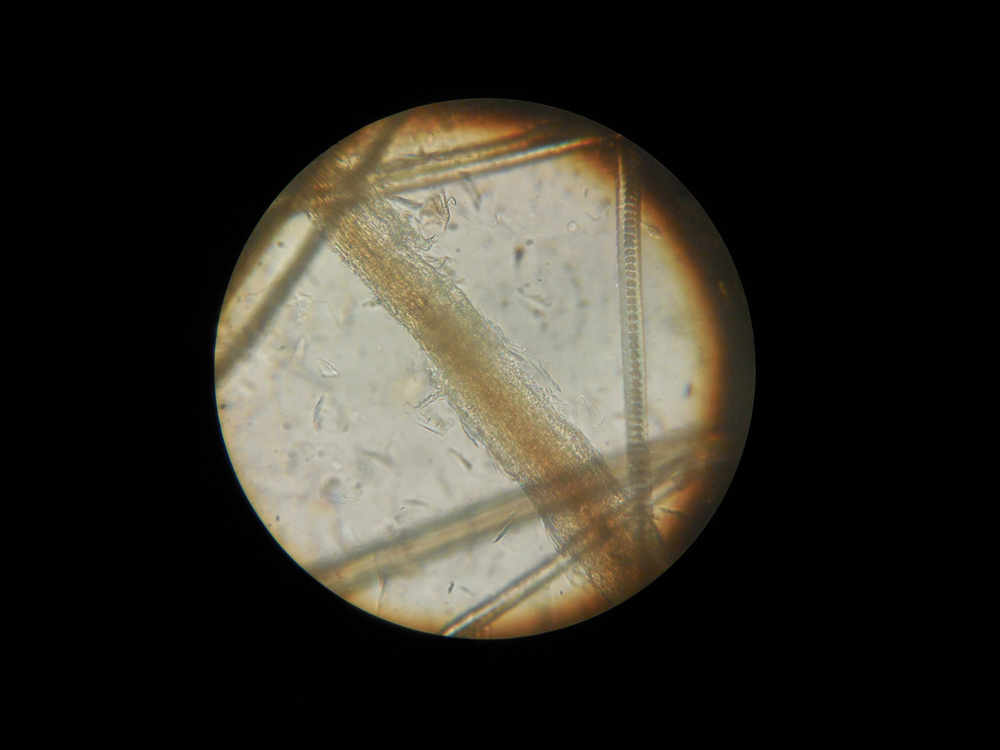

Для того чтобы поставить правильный диагноз, специалист сопоставляет данные клинического осмотра кошки и лабораторных исследований. В лабораторию отправляются соскобы с пораженных участков кожи, которые не подвергались лечению. Паталогический материал вначале микроскопируют, затем высевают на специальные среды. На основании полученных результатов уже ставится окончательный диагноз.